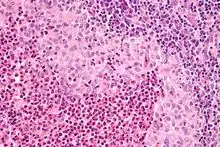

| Micrograph showing a Langerhans cell histiocytosis with the characteristic reniform Langerhans cells accompanied by abundant eosinophils. H&E stain. | |

Diagnosis is confirmed histologically by tissue biopsy. Hematoxylin-eosin stain of biopsy slide will show features of Langerhans Cell e.g. distinct cell margin, pink granular cytoplasm.[33] Presence of Birbeck granules on electron microscopy and immuno-cytochemical features e. g. CD1 positivity are more specific. Initially routine blood tests e.g. full blood count, liver function test, U&Es, bone profile are done to determine disease extent and rule out other causes.[34]